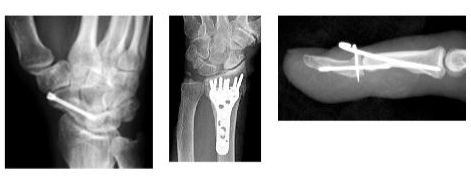

【 手外科、肘関節外科、末梢神経疾患、マイクロサージャリー 】

《手外科》

《肘関節外科》

《末梢神経疾患》

《マイクロサージャリー》

術後は理学・作業療法士と相談をしながらリハビリテーションを行ないます。